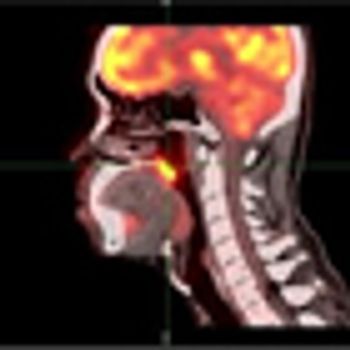

Neck dissection may no longer be the only surgical option for pathologic staging of the neck in patients with oral cavity squamous cell carcinoma, according to a new study.

More than one-third of patients with oropharyngeal cancer were seropositive for HPV16 E6 an average of 6 years prior to their cancer diagnosis compared with less than 1% of healthy controls, a new study has found.

Prophylactic use of the SSRI escitalopram decreased the occurrence of depression in patients with head and neck cancers by 50% and resulted in significantly improved quality of life for 3 months after drug cessation, according to the results of the PROTECT trial.